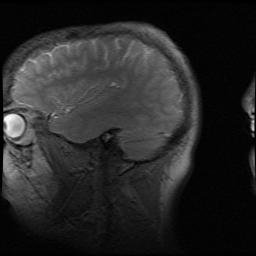

Here is my brain. You can’t see much. Feel free to make jokes about that, I’ve set myself up nicely with that last sentence!

my-brain1

These are MRI scan images from a routine checkup I had about 3 years ago. I suppose you can consider it a game of “Mystery MRI slices”, but one in which I give you the answer (my brain). You can see lots of cool anatomy here; if you know your anatomy feel free to mention what’s visible (or not) in the Comments, and make jokes– I will probably enjoy any of them. I like self-deprecatory humour. And happily, I checked out fine in that scan, and continue to be fine… relatively. I’m not the same person I was >10 years ago— in 2002 I got married (but missed my bachelor party because I was hospitalized for another problem), got an important paper (“Tyrannosaurus was not a fast runner”) published in Nature that changed my career (and arguably got me my job today), had this Really Bad thing happen, and plenty more. It was an eventful year.

my-brain2